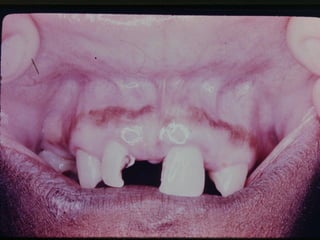

Pigmentação Melânica

• Características Clínicas